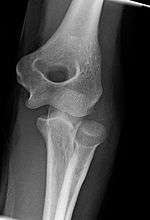

Development during childhood and adolescence

The elbow undergoes dynamic development of ossification centers through infancy and adolescence, with the order of both the appearance and fusion of the apophyseal growth centers being crucial in assessment of the pediatric elbow on radiograph, in order to distinguish a traumatic fracture or apophyseal separation from normal development. The order of appearance can be understood by the mnemonic CRITOE, referring to the capitellum, radial head, internal epicondyle, trochlea, olecranon, and external epicondyle at ages 1, 3, 5, 7, 9 and 11 years. These apophyseal centers then fuse during adolescence, with the internal epicondyle and olecranon fusing last. The ages of fusion are more variable than ossification, but normally occur at 13, 15, 17, 13, 16 and 13 years, respectively.[14] In addition, the presence of a joint effusion can be inferenced by the presence of the fat pad sign, a structure that is normally physiologically present, but pathologic when elevated by fluid, and always pathologic when posterior.[15]